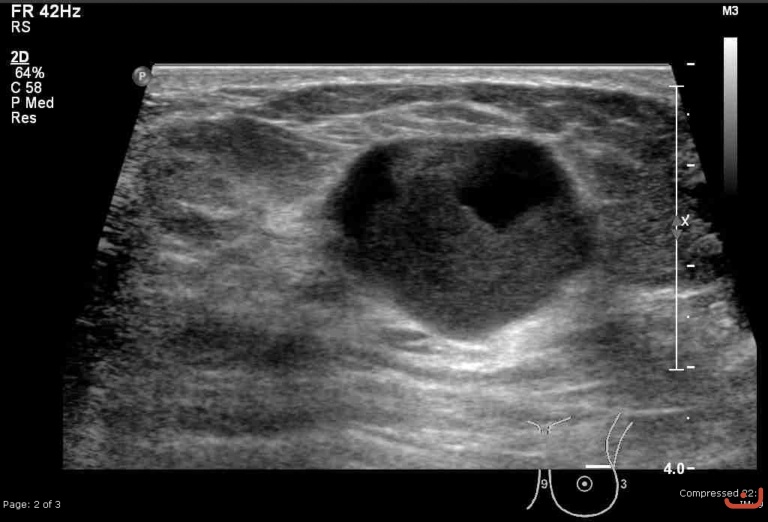

Malignant solid mass

Date

Thursday, 30 April 2015

File size of the original image

187.96 KB (768 x 522 px)